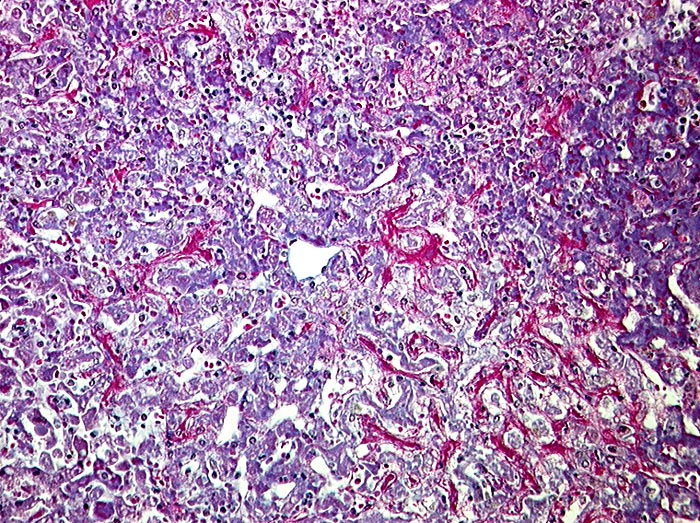

AP/ Subakute Stauung der Leber

Subakute Stauung der Leber

vaskulär / Durchblutungsstörung

Leber, Gallenwege, Pankreas

Leber

Leber HE

Pathologischer Befund